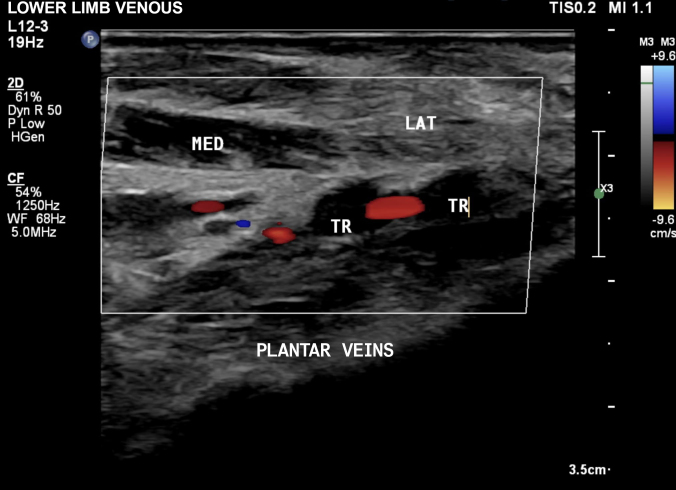

Plantar vein thrombosis is a vascular disease that affects the medial and/or lateral plantar veins. Its clinical manifestations are generally non-specific. However, it usually presents with pain in the plantar region, edema, and difficulty walking. The disease predominantly affects middle-aged females and is idiopathic in the majority of cases. The most commonly associated risk factors are recent surgical procedures, cancer, use of oral contraceptives, local trauma, and genetic disorders, such as hereditary thrombophilia. The gold standard diagnostic test is vascular ultrasound, evaluating venous compressibility. We report a case of venous thrombosis of the lateral plantar vein diagnosed with vascular ultrasound.